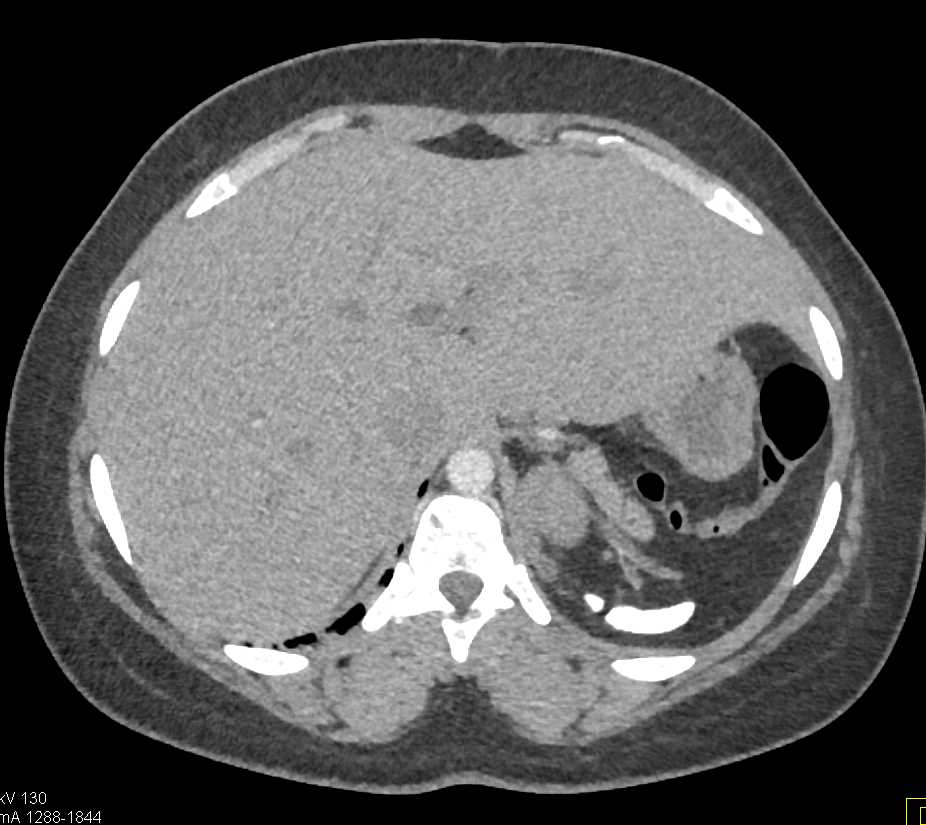

Gaucher's Spleen